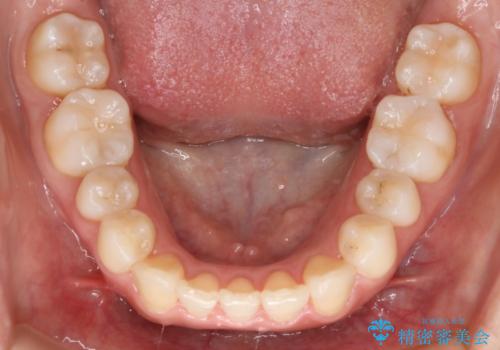

上顎の真ん中の歯の角度が、内側に傾いており、またその隣の歯が、唇側にずれてしまっていました。

上顎の前歯の傾きを改善することで、がたつきを治すためのスペースを確保しました。

また、それだけではがたつきを改善するスペースが不足していたため、歯の側面を削りがたつきを改善しました。